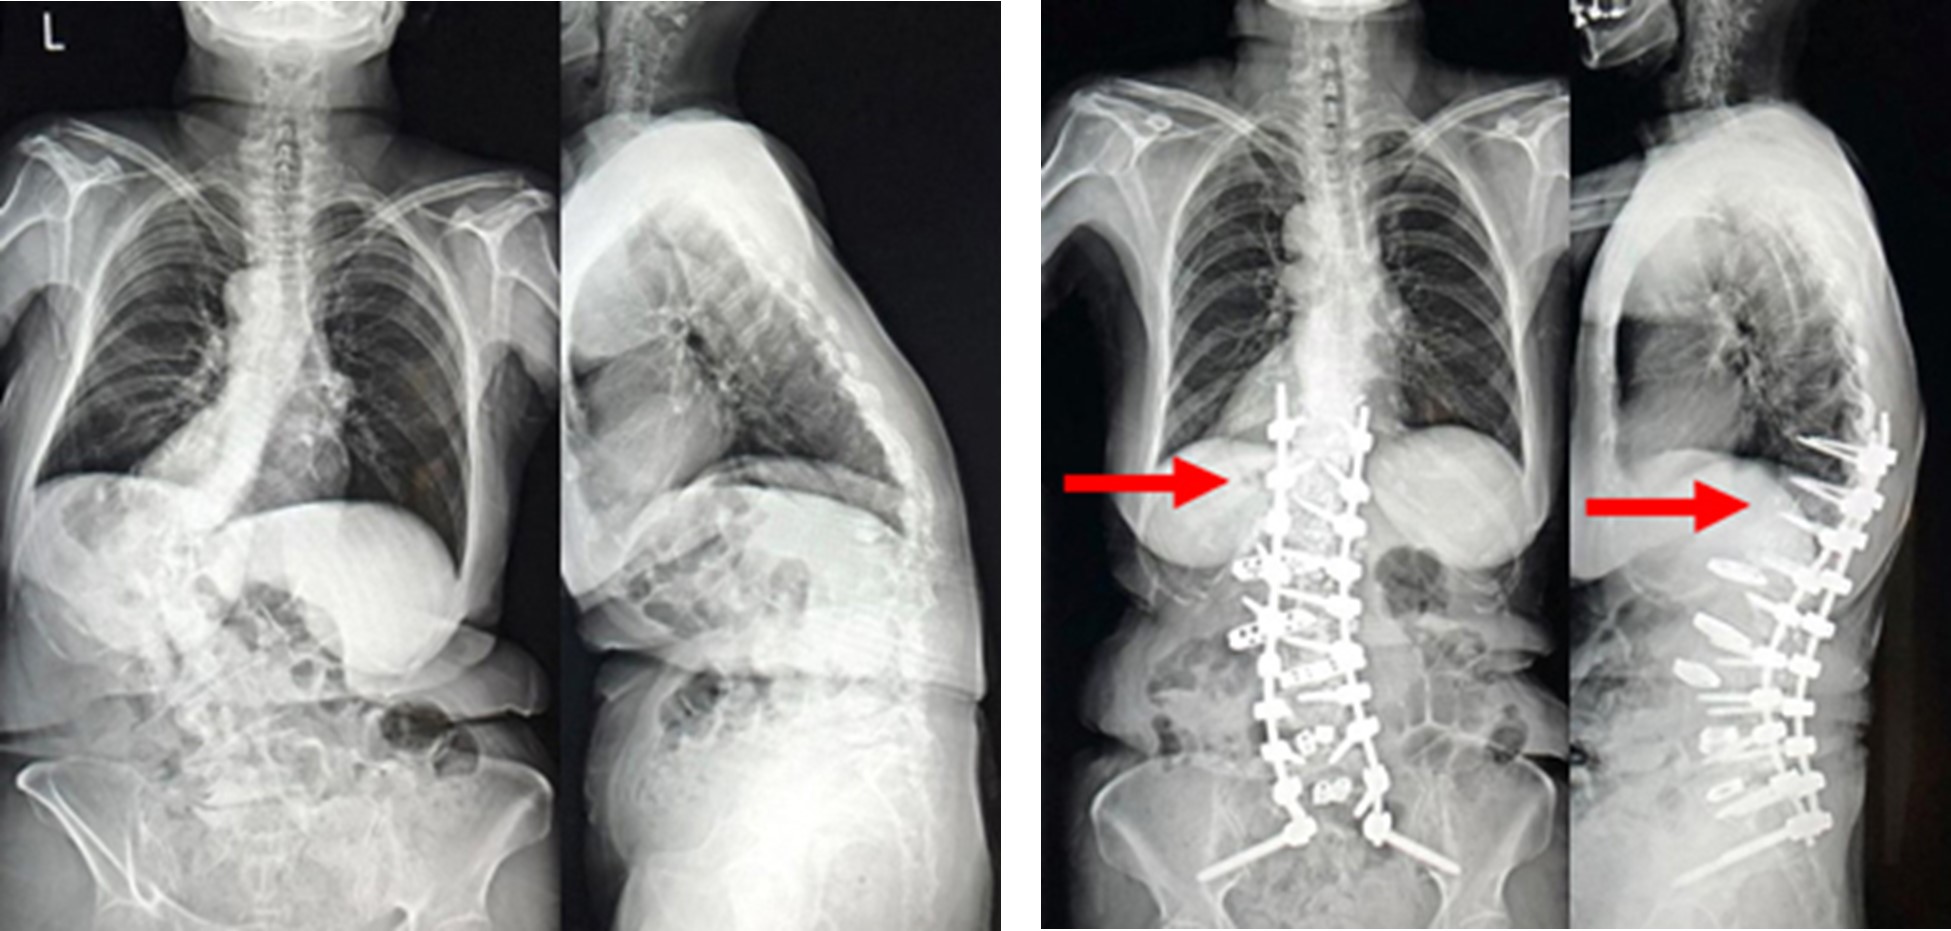

胸椎XLIF(エックスリフ)は、腰椎と同様に従来法に比べても身体に負担の少ない低侵襲での治療を可能にします。原則、手術翌日より起立・歩行を開始します。入院期間は最短で約7日程度ですが、病態により異なります。また、手術後は硬いコルセットを装着します。術前のX線画像。胸椎までおよぶ脊椎の変形を認めます。

図 (左)術前のX線画像

(右)術後のX線画像。胸椎と腰椎に対する側方経路椎体間固定術(XLIF:エックスリフ)を行い、良好な矯正が得られています。